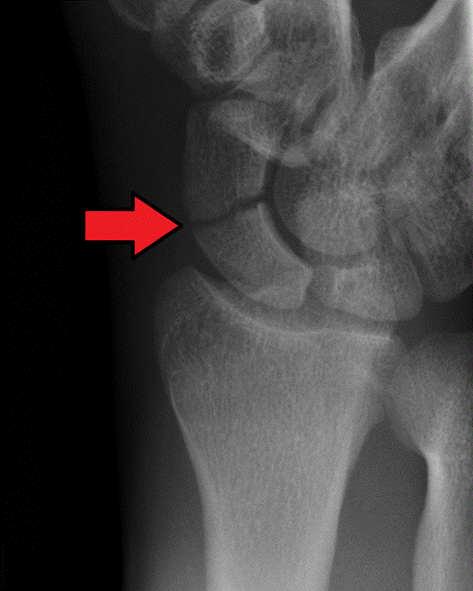

What view is this

ulnar deviation

What does the ulnar deviation best show

scaphoid fractures

scapholunate dislocations